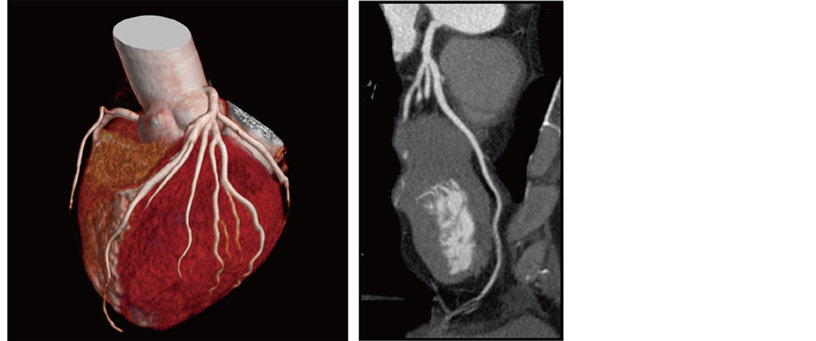

IntelliEC Cardiac reduces dose using electrocardiogram information. Dose modulation can be applied to minimize tube current during non-target phases, including resting phases of mid-diastole and end-systole.

Reconstructed cardiac phase 75%

CardioHarmony enhances cardiac CT workflow by automatically*6 detecting and reconstructing cardiac phases with minimal motion.